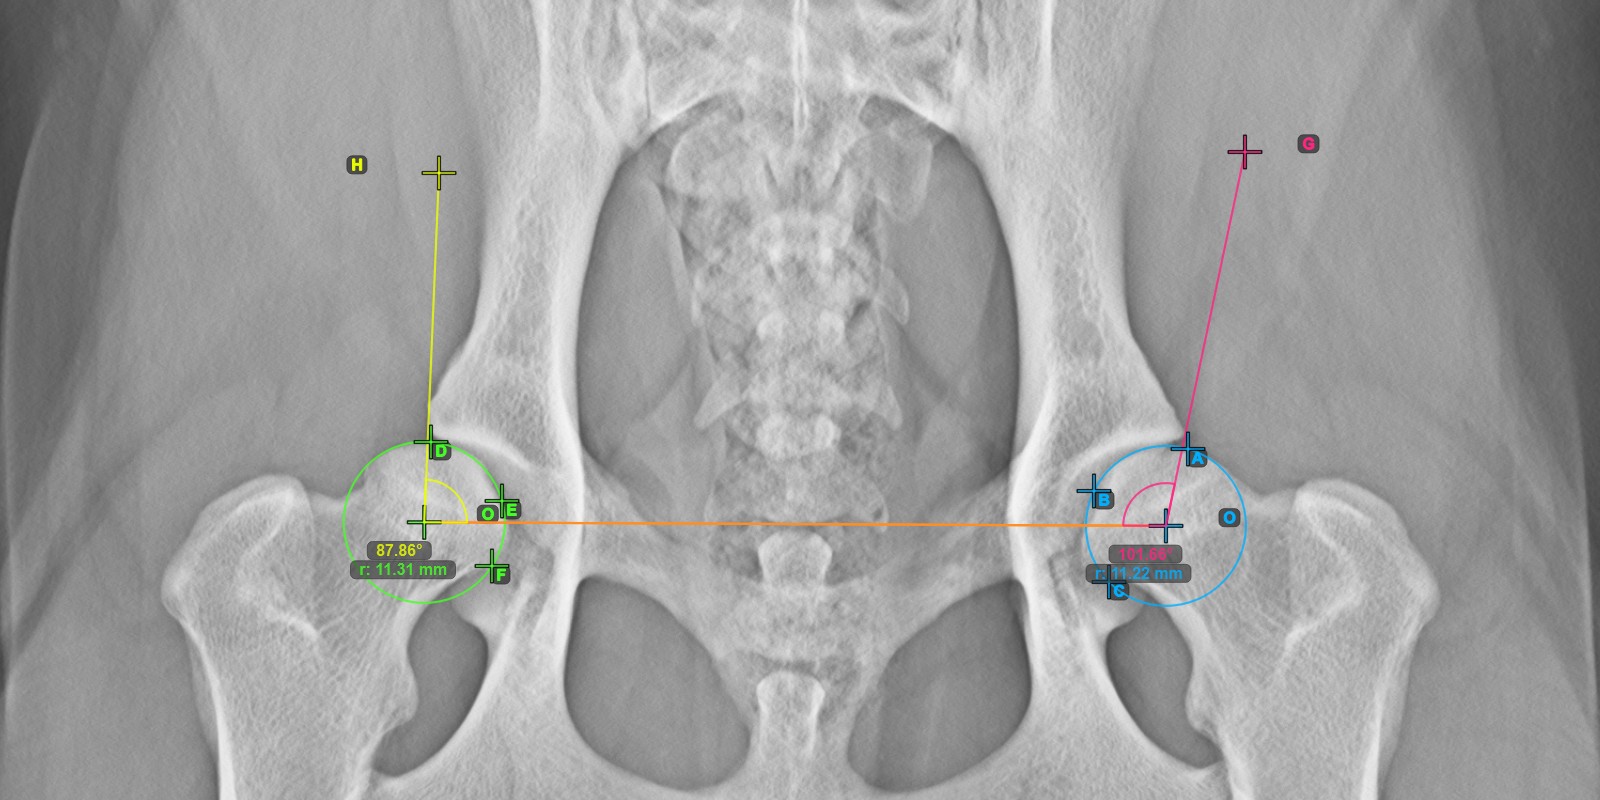

Das untenstehende Bild zeigt die typische Platzierung der drei Punkte auf der Gelenkfläche des rechten Caput Femoris.

Markieren Sie die drei Punkte auf der Gelenkfläche des rechten Caput Femoris (außerhalb der Fovea Capitilis). Unabhängig von der Reihenfolge stellen Sie sicher, dass der kranialste Punkt, der kaudalste Punkt und der Mittelpunkt des Femurkopfes markiert werden. Basierend auf den drei platzierten Punkten wird automatisch ein Kreis erstellt.

Das Bild unten zeigt die typische Platzierung der Linie und die berechnete Norberg-Winkel-Messung.

Die gezeichnete Linie muss eine Tangente an der effektiven Kante des linken Acetabulumknochens sein. Der Wert und der Bogen des Winkels werden automatisch berechnet.